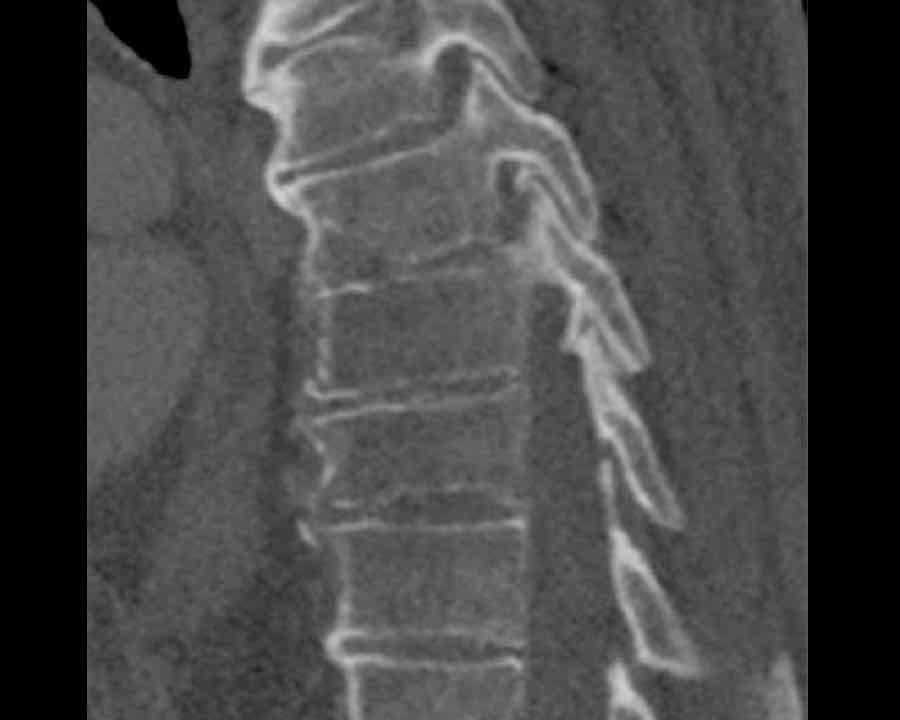

Scroll through images.

What are the findings?

Findings

- C injury? No.

- Signs of a rigid spine?

Yes, a B3 injury is very likely. - A subtle fracture on the anterior vertebral body.

Conclusion

Injury type B3.